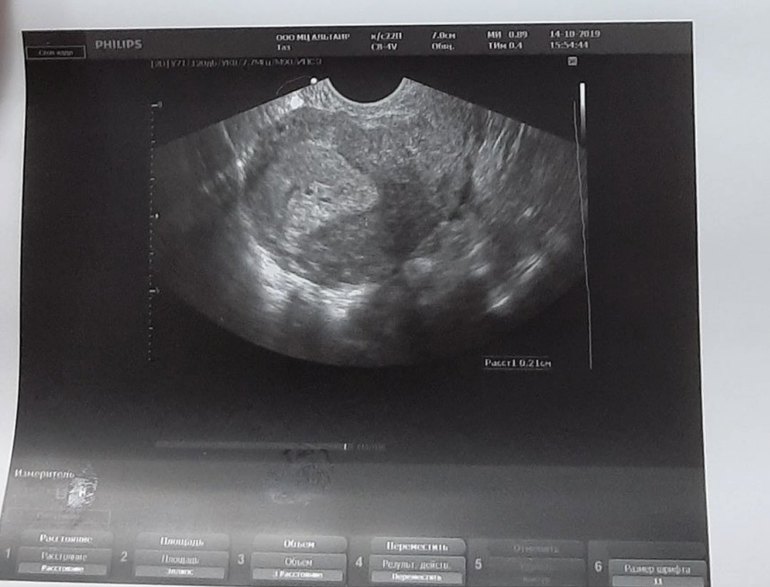

Сходила на узи, вместо спокойствия - еще больше вопросов(((

Вопросы про УЗИ, обследования и анализы: что, где, как, когда?Девочки, в общем сходила на узи. Беременность под вопросом.

Вообще узи без консультации было, поэтому и остаётся только читать да вглядываться. Меня смущает,что я вижу две чёткие точки...может ли это говорить о двойне?

Повторное УЗИ думаю лучше даже через пару недель?